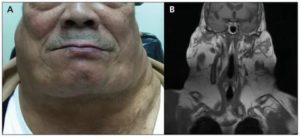

Первые признаки патологии у разных пациентов могут существенно отличаться. В большинстве случаев дебют заболевания связывают с разрастанием жировой прослойки в области затылка или же одновременно затылка и переднее-боковых областей шеи. Жировая подушка спускается по направлению к 7-му шейному позвонку, заполняет надключичные области, распространяется на верхнюю часть спины, формируя заметный «бычий» горб. Кольцевидная липома растет медленно, но с годами может достигать толщины 15 см и веса 6-8 кг.

- Методы медицинской визуализации. Получить необходимые сведения о характере разрастаний позволяют УЗИ мягких тканей, МРТ области головы и шеи, КТ области средостения. Наиболее предпочтительный и информативный метод исследования определяет врач на основании картины заболевания. Все методы позволяют оценить состояние органов средостения и шеи, оценить размеры жировых узлов, их доброкачественный характер.

Синдром Маделунга. Синдром Маделунга является разновидностью наследственного множественного липоматоза (диффузная липома шеи, доброкачественный симметричный липоматоз, жирная шея Маделунга, синдром Лонуа-Бансода). Жировые разрастания охватывают переднебоковые и задние поверхности шеи, далее распространяются на подбородок и грудную клетку. Иногда отмечаются множественные симметричные липоматозные узлы на туловище и конечностях. Течение обычно медленное, но иногда наблюдается быстрый рост опухолей. Боль возникает при значительном увеличении количества жировой ткани, когда сдавливаются периферические нервы. Нарушается венозный отток, могут сдавливаться гортань, глотка, что проявляется расстройством дыхания, дисфагией, дизартрией, стенокардией, псевдомиопатией, постепенным нарастанием слабости в мышцах конечностей. Болеют преимущественно мужчины в возрасте 35-40 лет. Лабораторные сдвиги не обнаруживаются. При гистологическом обследовании выявляют скопления жировой ткани нормальной структуры. Тип наследования – аутосомно-доминантный.